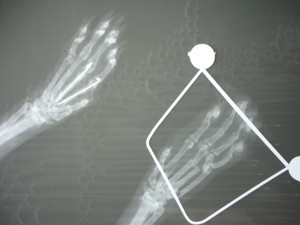

Cuando una imagen vale más que mil palabras

En ocasiones puede ser necesario conseguir imágenes que apoyen el diagnóstico del veterinario. La radiografía es un método sencillo para obtener las mismas y puede ser indispensable para estudiar ciertas regiones del organismo, fundamentalmente tórax, tejido óseo y en muchas ocasiones abdomen.

En ciertas patologías es muy importante la obtención de radiografías en proyección standard, sobretodo en traumatología, para ello puede ser preciso tranquilizar previamente al animal para conseguir una buena relajación muscular.

En nuestro centro contamos con un moderno aparato de RADIOGRAFÍA DIGITAL, que permite un mejor y más eficaz diagnóstico de tu mascota.